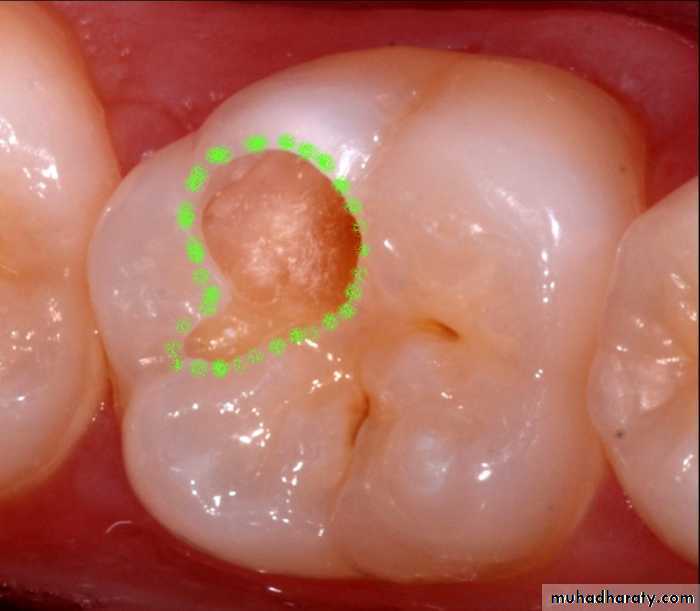

Advanced visual-Dye penetration method

In carious dentin, two layers of decalcification can be identified:One layer which is soft and cannot be remineralized

A second layer, which is hard with intermediate calcification and can be remineralized.

It is now clearly established that these dyes do not stain bacteria but instead stain the organic matrix of less mineralized dentin.

This make them less specific because dyes do not stain bacteria nor delineate (trace an outline) the bacterial front but stain collagen associated with less mineralized organic matrix.